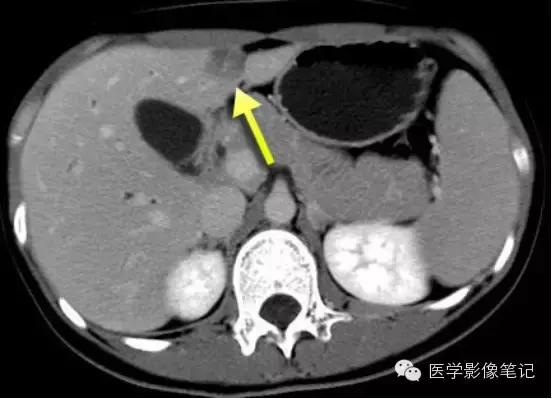

镰旁肝假病灶

多位于左叶内侧段或(和)左叶外侧段前缘镰状韧带旁。

机制:1、镰旁肝局部特殊血供因素;2、镰旁肝局部脂肪浸润。